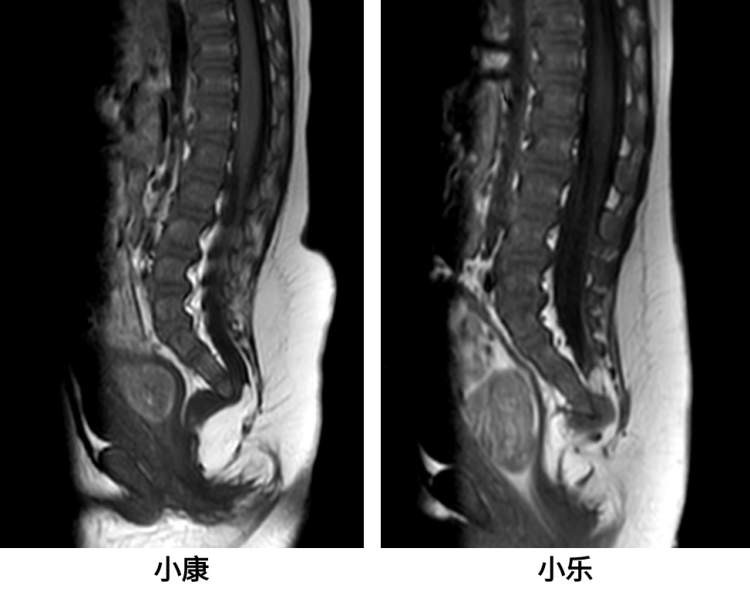

一对8个月大的双胞胎宝宝小康和小乐,因排便困难被确诊为罕见的Currarino三联征。在上海交通大学医学院附属新华医院多学科团队的精心诊治和联合手术下,两个宝宝成功战胜病魔,重获新生。Currarino三联征,这是一种包含骶骨发育不全、直肠肛门畸形和骶骨前肿物三种异常的先天性畸形。

更为少见的是,同卵双胞胎同时确诊为Currarino三联征。在查阅文献后发现,国际上仅有两例报道,国内尚无此类病例报道。不仅如此,小康和小乐还同时伴随了脊髓拴系综合征,这种病症若不及时治疗,亦可能导致神经损害和一系列严重后果。

小康和小乐虽然同患一种疾病,但各自的病情和治疗侧重点存在明显差异。小康的直肠肛门畸形较为严重,此次入院无法根治。首先由儿神经外科完成脊髓栓系松解术,随后再由儿普外科进行骶骨前方脂肪瘤的切除及肠道手术。而小乐的肛门狭窄状况相对良好,可以在一次麻醉的情况下,同时处理脊髓栓系及骶前肿物两部位的病变。针对不同的情况,上海新华医院的多学科专家团队围绕双胞胎宝宝的病情全面评估,不断完善手术方案。3月15日,在麻醉重症医学科副主任医师杜溢和手术室高碧蓉护士长的协调下,联合手术治疗顺利进行。术后,小康和小乐的情况良好,已于3月22日顺利出院。